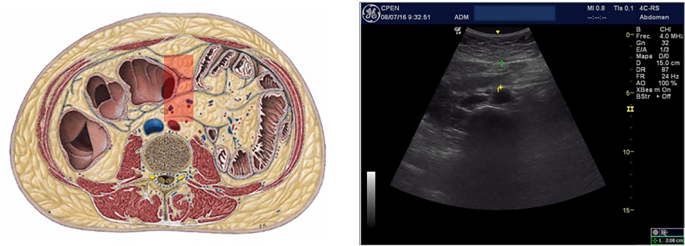

Deeper inside the abdominal cavity, intra-peritoneal fat should be understood as 2 coexisting, melted, fat tissues: Mesenteric fat, rich in lymphoid and connective tissue that protects and fix abdominal organs to the dorso-lumbar posterior wall22 and Omental fat, metabolically active, surrounding bowels. This intraperitoneal fat is usually (but wrongly) called “visceral fat”, concept that should only refer to the fatty infiltration of solid organs such as liver, pancreas or kidney. It is known that Omental fat interacts with upper gastrointestinal tract and its microbiota, inducing insulin-resistance23 and is related with increased cardiovascular risk24. A specific cut-off measure for Omental fat thickness of 37 mm (women) and 54 mm (men), for Metabolic syndrome risk, has been proposed using ROC curves analysis11 (Fig. 2).

Omental (periaortic) fat.

Finally, in the retroperitoneal space, peri and para-renal fat (spliced by a fascia) surround both kidneys25. Perirenal fat thickness has also been related to Metabolic syndrome and cardiovascular risk11 with a proposed cut-off point of 17 mm (women) and 22.5 mm (men) (Fig. 3).

Perirenal fat.

Ultrasound measurements